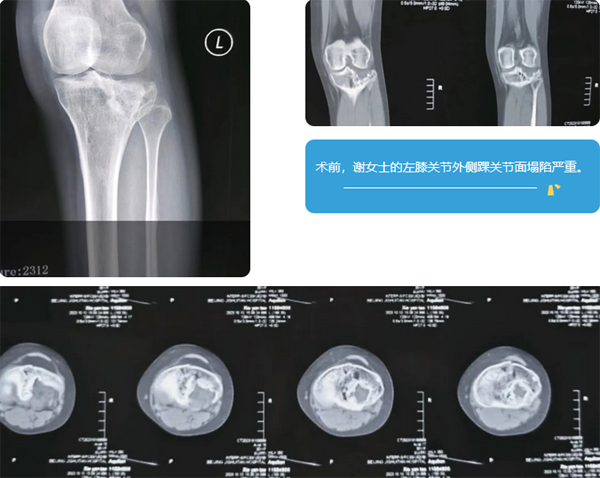

31岁的谢女士,六年前在怀孕期间不幸摔伤左侧膝关节,导致一个外侧髁出现胫骨平台重度塌陷骨折。出于对腹中胎儿的担心,这位准妈妈未接受正常的检查和治疗。六年来,谢女士行走愈发困难,主要表现为明显的膝关节不稳定和疼痛,在当地医院多方诊治,未能寻获明确有效的解决方案。

两个多月前,谢女士得知北京积水潭医院创伤骨科毛玉江主任医师在陈旧性胫骨平台骨折领域治疗经验丰富,于是来院就诊。经过体格检查、X线平片、CT以及MRI影像的仔细评估和分析,毛玉江主任医师认为谢女士的病情较为复杂。

特殊之处在于,其外髁关节面塌陷范围广,约占外侧平台的3/4,且受损程度严重,塌陷最低点距离关节面接近3cm。此外,由于病程拖延太久,六年的非正常磨损使得其胫骨外髁关节软骨与半月板已基本毁损。